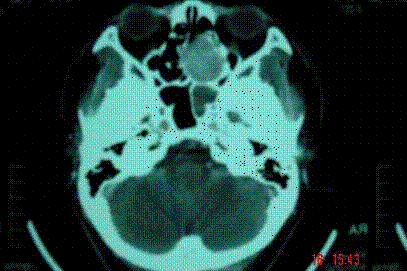

问题 病历摘要: 患者男,37岁,因右鼻塞伴涕中带血4个月入院,患者4个月前始右鼻塞,为间断性,偶有涕中带血,时有流脓性分泌物,并症状渐渐加重。但发病以来患者无头痛、面部麻木和疼痛,无复视及流泪,张口正常。检查:右侧鼻腔总鼻道可见表面光滑、质中、粉红色肿物,触之不易出血。鼻咽黏膜光滑,未见新生物和黏膜糜烂。颈部未及淋巴结肿大。 在活检结果未出来前,你考虑哪些疾病? 提示:鼻窦CT显示:右侧中鼻道-上颌窦窦口区见一软组织密度肿块影,大小约35×5mm,增强扫描中等强化。肿块向外侧破坏上颌窦内侧壁突入上颌窦,向内侧破坏鼻中隔累及左侧鼻腔,向上破坏右侧筛窦下壁。右侧中鼻甲骨质破坏。

选项 A、软骨瘤 B、鼻窦恶性肿瘤 C、血管瘤 D、筛窦黏液性囊肿 E、筛窦浆液性囊肿 F、骨瘤 G、出血性坏死息肉 H、鼻窦真菌病

答案 BDH